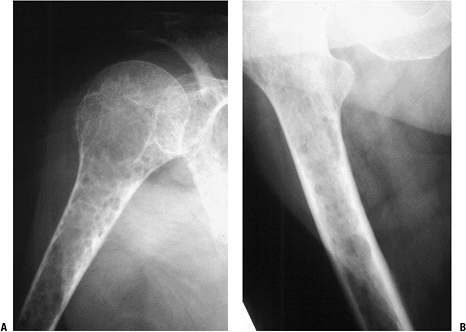

Biopsy showed metastatic adenocarcinoma. (B) Computed tomography scan of the lung revealed a mediastinal mass consistent with a lung carcinoma primary. Figure 8-5 A lytic, relatively well-defined metastatic lesion of the right humerus in a patient with renal cell carcinoma. Figure 8-5 A lytic, relatively well-defined metastatic lesion of the right humerus in a patient with renal cell carcinoma.![]() Figure 8-6 A pelvic radiograph shows typical blastic metastases from prostate cancer.P.237 Figure 8-6 A pelvic radiograph shows typical blastic metastases from prostate cancer.P.237 Figure 8-7 Figure 8-7

Multiple bone lesions in a woman with breast cancer show the wide

variation in appearance of breast cancer metastases to bone, from the

predominately lytic appearance in the ischium, the mixed lytic and

blastic proximal femur metastases, and the sclerotic distal femur

metastases.![]() Figure 8-8 Figure 8-8